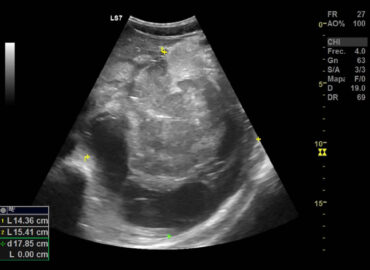

Paciente masculino de 25 años, sano previo, con dolor abdominal